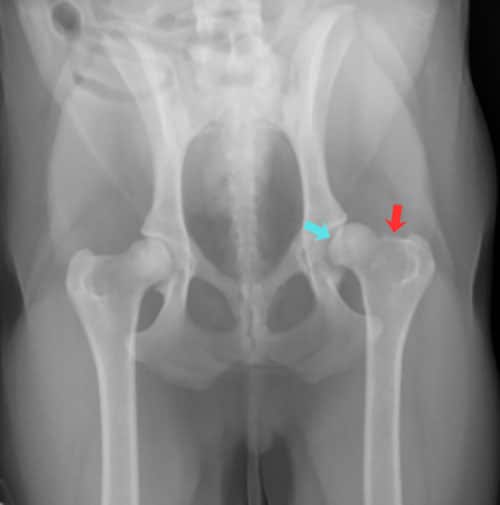

While humans generally develop primary arthritis, dogs actually get secondary osteoarthritis – arthritis that forms due to an underlying orthopedic problem. Conditions like hip dysplasia, elbow dysplasia, or cruciate ligament injuries can damage a joint early in life, setting the stage for joint degeneration and years of pain.

A recent study1 published in 2024 found that 40% of dogs under four years old already have evidence of osteoarthritis on X-rays in at least one joint. More than 30% of dogs had arthritis in at least two or more joints.

In that same study, only about one quarter of the dogs with arthritis visible on x-rays showed obvious signs of pain during a veterinary exam. And even when they did show signs of pain, owners only recognized those signs about 30% of the time.